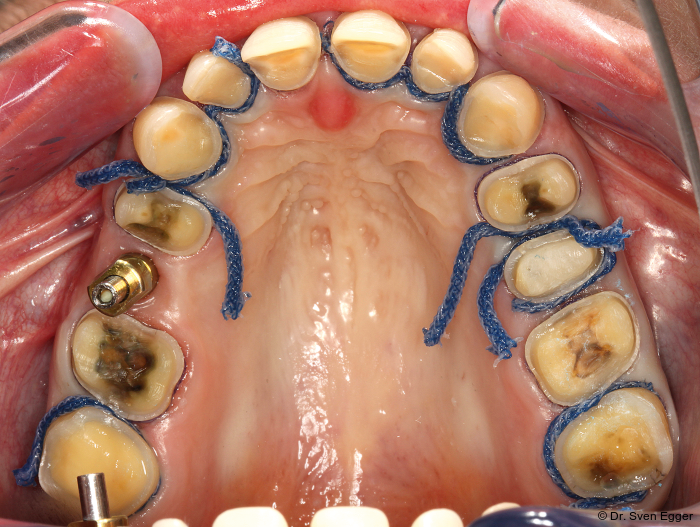

- Zweifache Abdrucknahme der präparierten Zähne mittels Doppelfadentechnik: Einbringen eines ersten, getränkten (Racestyptine solution, Septodont) Fadens (Ultrapak 0, Ultradent), über welchen ein zweiter getränkter Faden größeren Durchmessers gelegt wird (Ultrapak 1, Ultradent). Ca. zehn Minuten Wartezeit bis zur Abdrucknahme mit den gelegten Fäden.

- Die Abdrucknahme erfolgt nach Entfernung des zuletzt gelegten Fadens (der zuerst gelegte Faden geringeren Durchmessers verbleibt im Sulkus) mittels eines A-Silikons in Doppelmischtechnik einzeitig: Umspritzung der präparierten Zähne mit dünnfließendem Material (Express Ultra-Light Body, 3M Espe) und Einbringen des schwerfließenden Materials, (Express Penta Putty, 3M Espe) in einen Abdrucklöffel (Rim Lock, DeTrey; Abb.13).